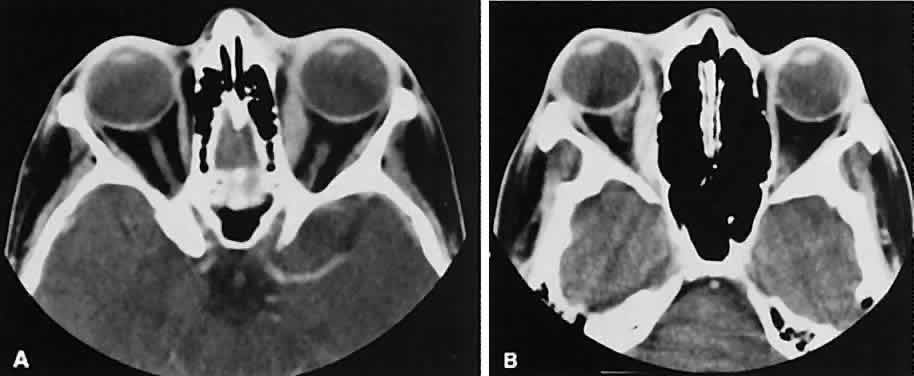

Graves' orbitopathy probably represents the most frequent cause of proptosis and EOM enlargement. The CT findings are fairly stereotyped and typically display various degrees of EOM enlargement (Fig. 7). The inferior rectus muscle usually is affected earliest, followed by the medial rectus, superior rectus, and finally the lateral rectus muscle. Rootman and colleagues13 noted more frequent involvement of the superior rectus/levator and medial rectus muscles than what had been reported previously with Graves' orbitopathy. These muscles can be affected in isolation, with the exception of the lateral rectus. To the best of our knowledge, isolated lateral rectus enlargement has not been reported in Graves' orbitopathy and in our experience usually is associated with a sphenoid wing meningioma.

Fig. 7. Graves' orbitopathy with two variations. Axial (A) and coronal (B) views show symmetric fusiform enlargement of the extraocular muscles with tapered muscle insertions. Note the predominant enlargement of the inferior, medial, and superior rectus muscles with lesser involvement of the lateral rectus muscle, a frequent pattern of enlargement in Graves' orbitopathy. Axial (C) and coronal (D) views of Graves' orbitopathy with expansion of retrobulbar ground substance and relative sparing of the extraocular muscles.

CT evidence of Graves' orbitopathy tends to be bilateral. Approximately 86% of patients with unilateral clinical findings have bilateral CT findings in our experience, which is consistent with the experience of others.42

Morphologically, the EOM belly is enlarged, with a gradual tapering toward and sparing of the tendinous portion of the muscle. Tendon involvement is a typical feature of orbital myositis. Tendon involvement helps to differentiate this lesion from Graves' orbitopathy, although Rootman and Nugent43 have noted a rare patient with Graves' orbitopathy with this finding.